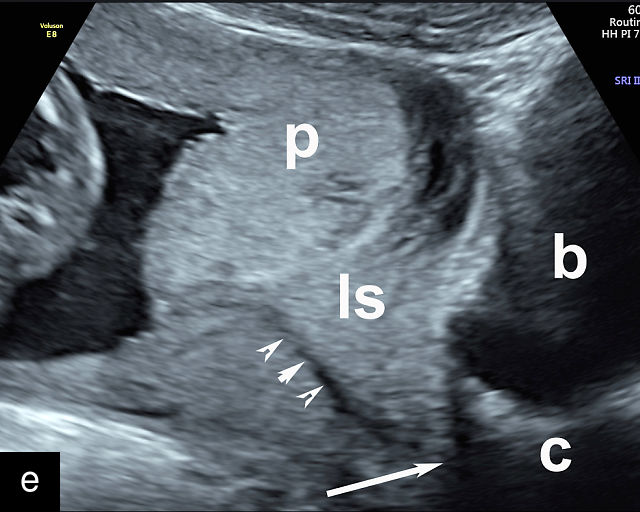

In the past, placenta previa was classified as complete, partial, marginal or low-lying.50,61 However, with advancements in ultrasound technology allowing precise assessment of the relationship between the placenta and the internal cervical os, the classification has been simplified.67 Placenta previa now refers to cases in which the placenta overlies the internal os to any degree, while low-lying placenta describes cases in which the lower placental edge lies within 2 cm of the internal os (Figure 5).51,66,67

5

Placenta previa and low-lying placenta. (a) Transabdominal grayscale ultrasound image suspicious for placenta previa. The placenta (PL) appears to overlie the internal cervical os (CX). Note the time stamp: 2:19:37. (b) Transvaginal ultrasound of the same patient taken approximately 50 minutes later. Note the time stamp: 3:10:25. The internal os and the lower placental edge are both clearly seen, and the placenta does not overlie the internal os. Because the lower placental edge is 1.93 cm from the internal os, it will likely resolve by the third trimester. (c) Transabdominal grayscale ultrasound of placenta previa. The placenta (p) covers the cervix, but the cervix, especially the internal os, cannot be visualized due to shadowing. (d) Transabdominal grayscale ultrasound of placenta previa. The placenta (p) covers the cervix (c) but shadowing obscures adequate visualization. The internal os is indicated by the arrow. (e) False-positive image of placenta previa on transabdominal grayscale ultrasound. The bladder (b) is full, pushing the anterior and posterior walls of the lower uterine segment (ls) together making it appear that the placenta (p) overlies the internal os of the cervix. In reality, the line depicted by the arrowheads is where the anterior and posterior walls of the lower segment are in proximity to each other. The cervix is much lower and is obscured by shadowing (c). (f) Transabdominal grayscale ultrasound image of placenta previa. The placenta (p) covers the cervix (c), but the cervix, especially the internal os, cannot be visualized due to shadowing. b, bladder. (g) Transvaginal grayscale ultrasound image of placenta previa. The placenta (p) completely covers the internal os (arrow) of the cervix (c). The internal os can be seen clearly. h, fetal head. (h) Transvaginal grayscale ultrasound image of posterior low-lying placenta (p). The lower placental edge is clearly seen and is 1.56 cm from the internal os (arrow) of the cervix (c). The placental edge and the internal os are clearly seen. h, fetal head. (i) Transvaginal grayscale ultrasound image of a posterior placenta previa (p). The internal cervical os is clearly seen (arrow). c, cervix. (j) Transvaginal grayscale ultrasound image of an anterior placenta previa (p). The internal cervical os is clearly seen (arrow). c, cervix; h, fetal head. (k) Transvaginal grayscale ultrasound image of a posterior placenta that was thought to be low-lying on transabdominal sonography but could not be adequately assessed. This examination clearly shows the lower edge of the placenta (p) to be 2.18 cm from the internal os (arrow) of the cervix, firmly establishing that the placenta is not low-lying and allowing the patient to undergo labor safely and deliver vaginally. c, cervix. (l) Transvaginal grayscale ultrasound image of placenta previa. The placenta (p) completely covers the internal os (arrow) of the cervix (c). The internal os can be seen clearly.

Most cases of placenta previa will be suspected prenatally by transabdominal ultrasound.49 However, this approach has several limitations and may be inaccurate.72,73,74 because the relationship between the placenta and the internal cervical os may be difficult to assess by transabdominal ultrasound.72,73,74 The bladder may be full, pushing the anterior and posterior walls of the lower uterine segment together, falsely creating the impression of a placenta previa (Figure 5e).61 There may be considerable shadowing, including by the fetal presenting part, which may limit the accuracy of transabdominal ultrasound (Figure 5d,f).75 Posterior placentas may be more difficult to assess.

Transvaginal ultrasound overcomes these limitations (Figure 5g–l).72,73,74,76 The probe is inserted into the vagina and therefore is closer to the region of interest.51,61 In addition, transvaginal transducers have higher frequencies and superior resolution compared to transabdominal transducers. Transvaginal ultrasound is safe and is not associated with increased bleeding.72,73,74,75,76 As such, transvaginal ultrasound should be the imaging modality of choice whenever there is suspicion of placenta previa.49,67,77